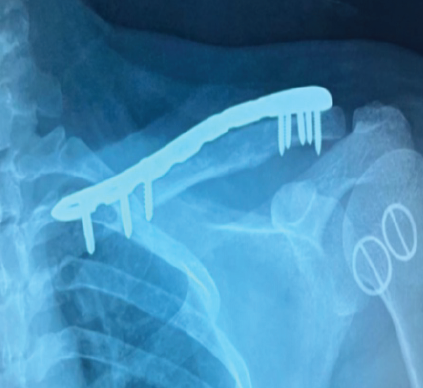

Spontaneous Remodeling of Posterior Sternoclavicular Joint Dislocations in Skeletally Immature Patients: A Case Report

Abdalla O. Abdalla , Eoin Fahey , Rebecca Lyons , David Morrissey